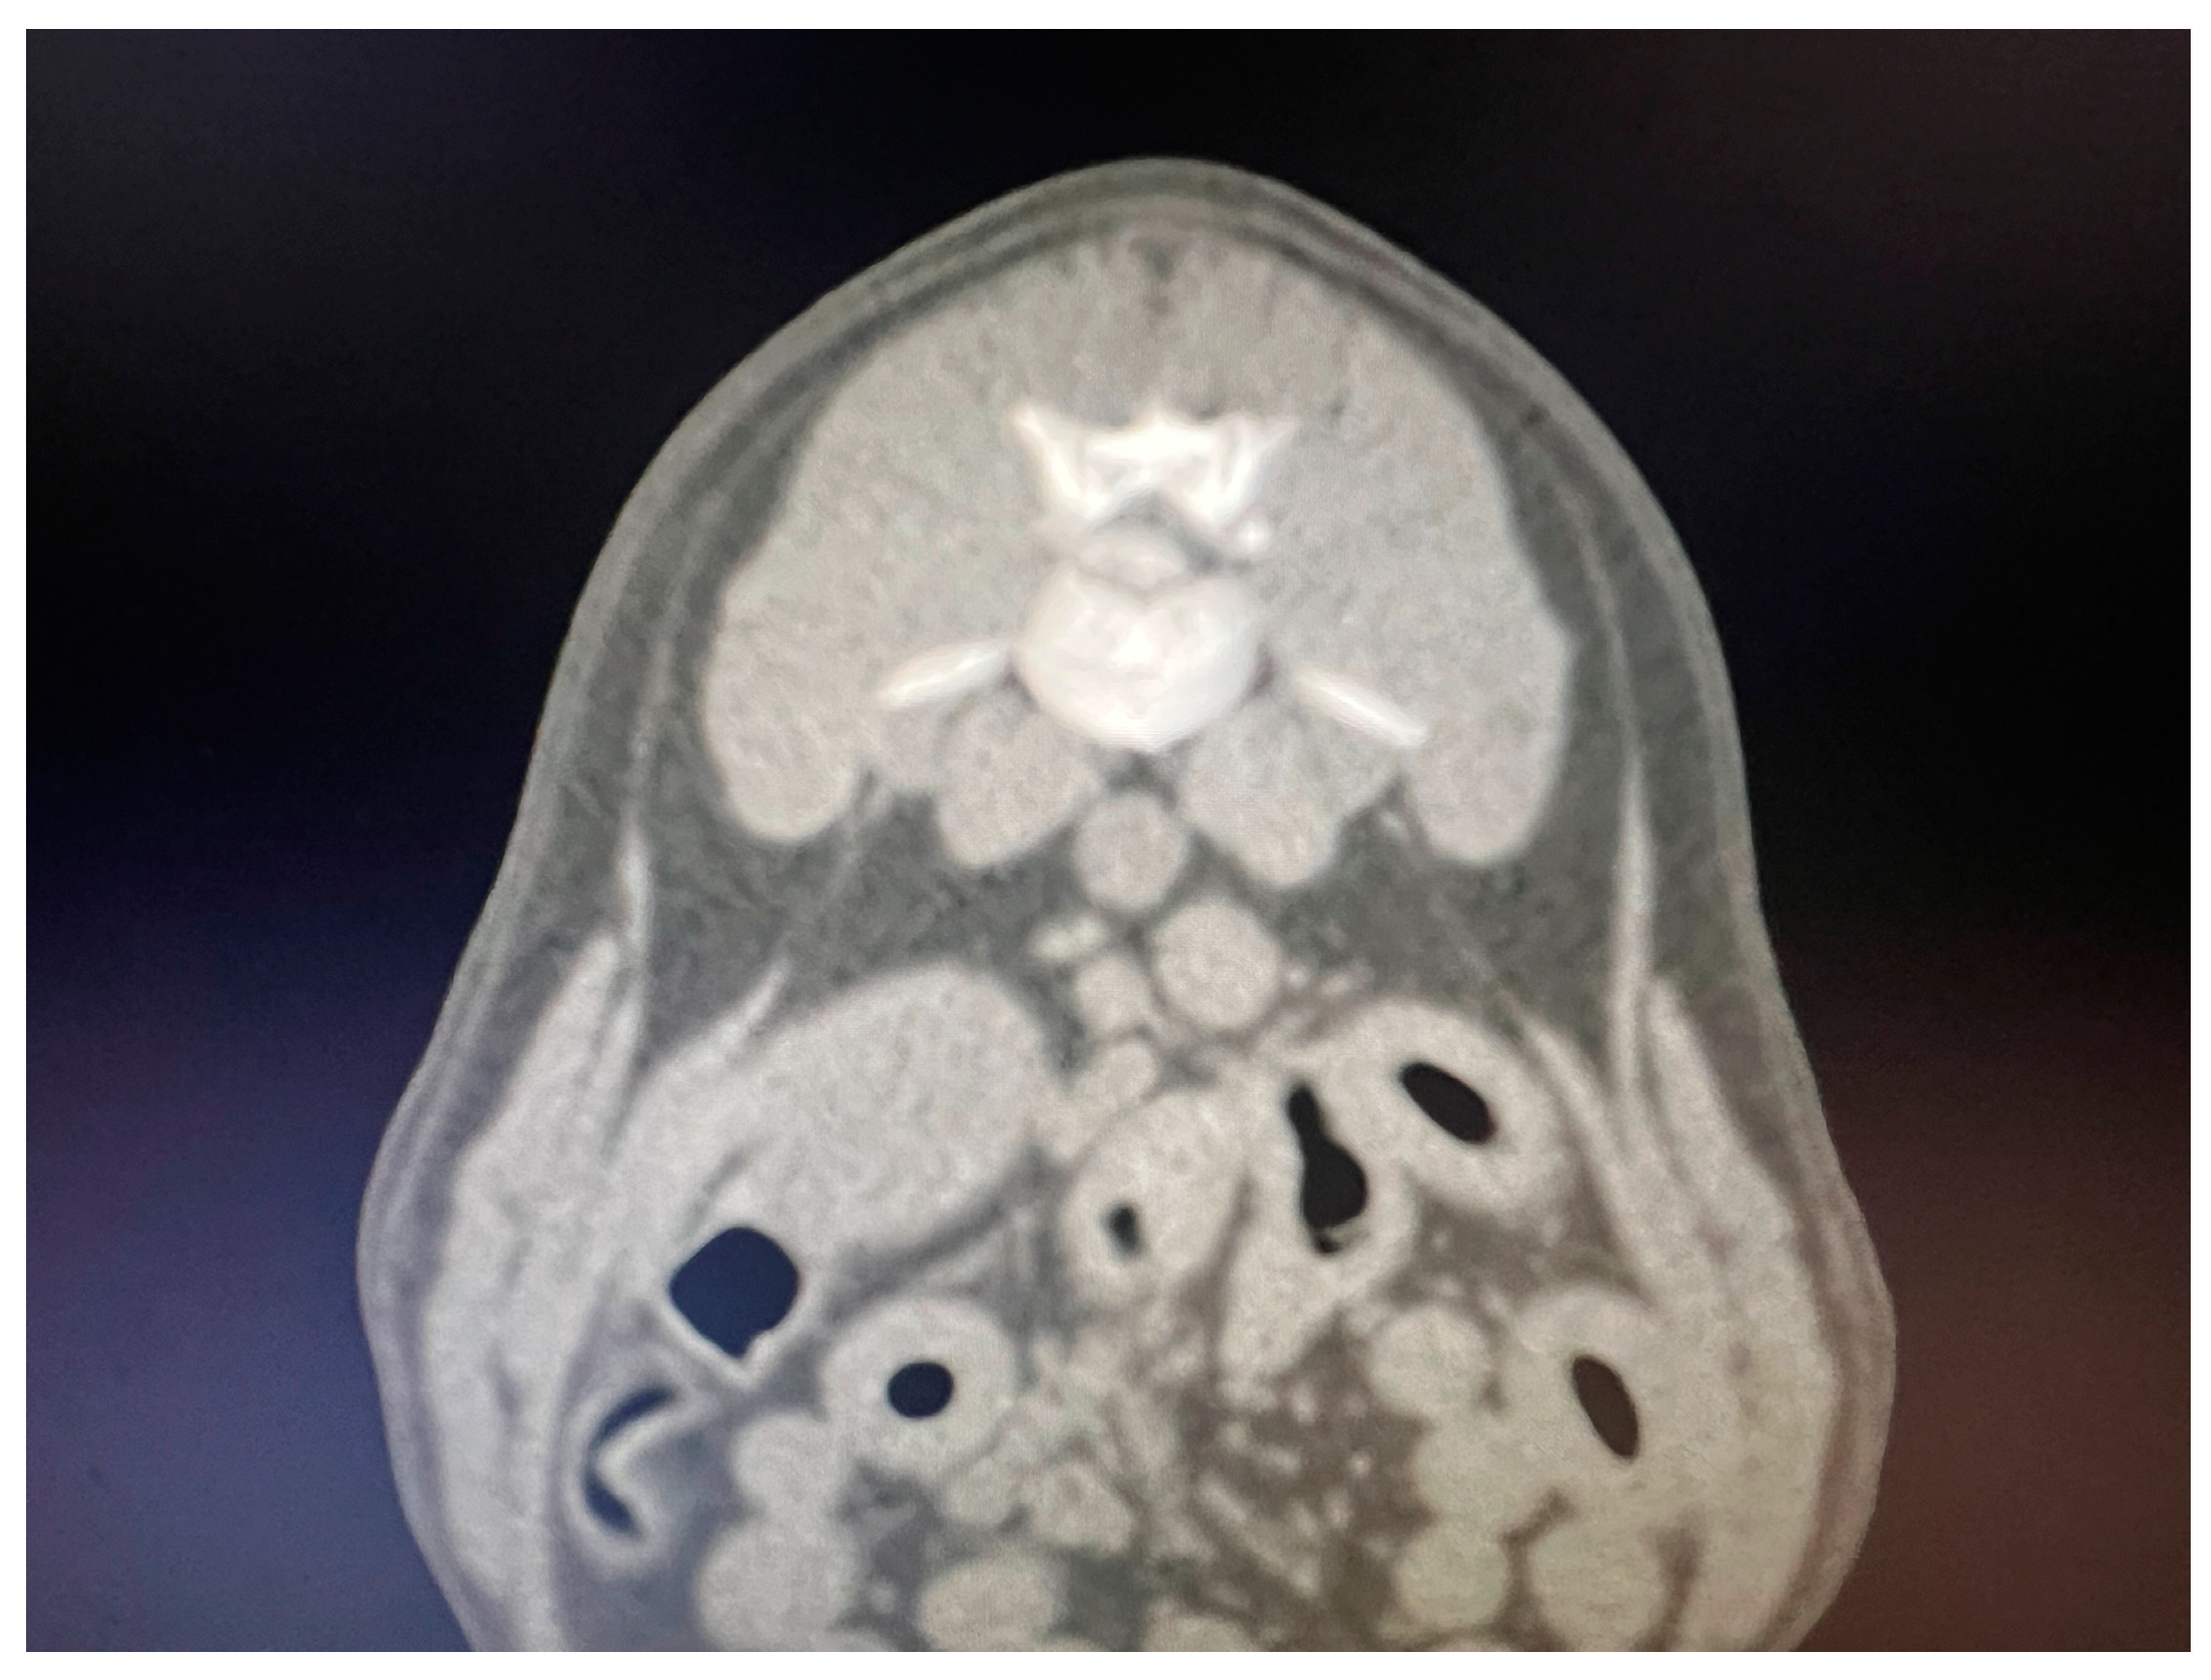

Figure 1.

Transversal CT scan image showing a L1-L2 herniated disc.